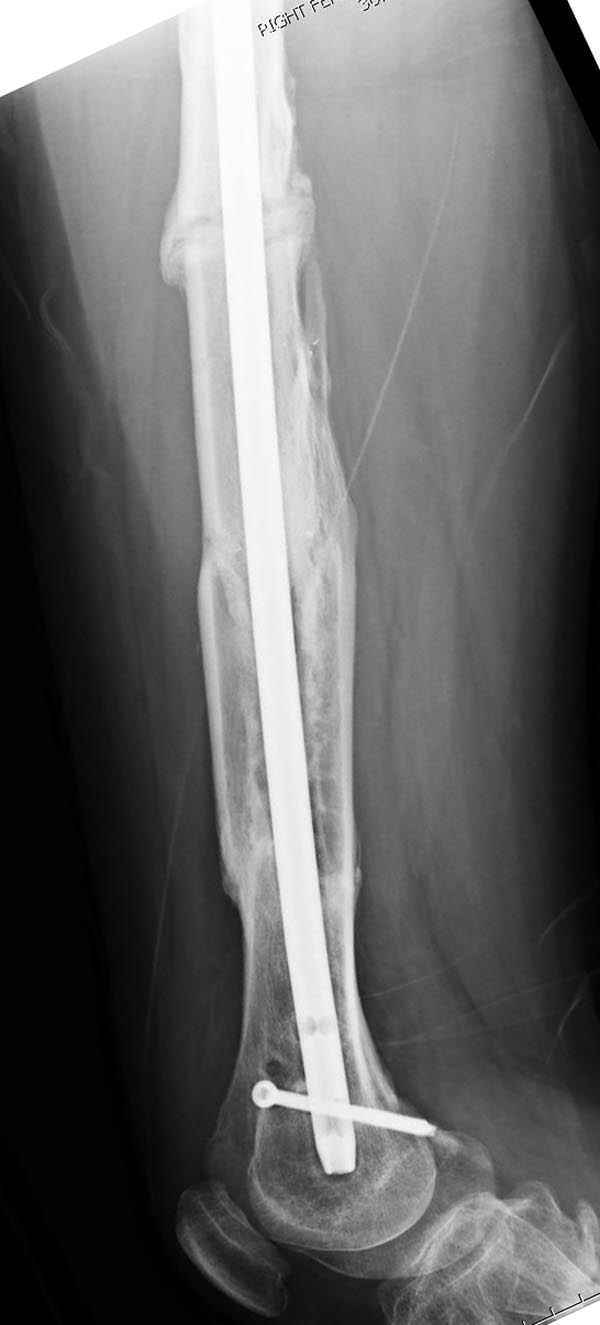

Инфекция канала и стрессовый перелом:

Представляю снимки больного с политравмой: леченного в другом мед.учреждении по поводу открытого перелома бедра, сперва аппаратом наружной фиксации, затем пластиной. Обратился к нам через 8 месяцев после удаления пластины с проблемой несросщего перелома бедренной кости, без клинических проявлении к инфицированию (не все снимки сохранены)

Рутинный интрамедуллярный остеосинтез с расверливанием и с фиксацией реконструктивным трокантерик штифтом (рис №1, №2),

если первые 4 месяца послеоперационного периода проходил без проблем, но на 5 месяце появились боли в дистальном отделе бедра и температура, т.е. симптомы медуллярного инфицирования (рис №3, №4).

Замена реконструктивного штифта “Custom made Nail” с антибиотиком (рис №5, №6),

после промывки канала с рассверливанием внутреннего кортекса, через 4 недели антибиотический штифт удалили, оспалителный процесс остановлен и бедро сросся.

Мы не дождались “Happy End”, у больного IQ в пределах 70%, через 6 месяцев вернулся после небольшой травмы, споткнувшись получил перелом

того же бедра (рис №7).

На следующий день произвели интрамедуллярный остеосинтез: этапы во время операции (рис №8, №9)

и последующих снимках (рис №10, 11, 12, 13) перелом сростается и передвигается с полной нагрузкой.

При обзоре причин перелома, на снимке №2 обнаружили, что один из стержней аппарата наружной фиксации проходил только через передний кортекальный слой, что создало стрессовую зону на бедре и в результате перелом из-за незначительной травмы.